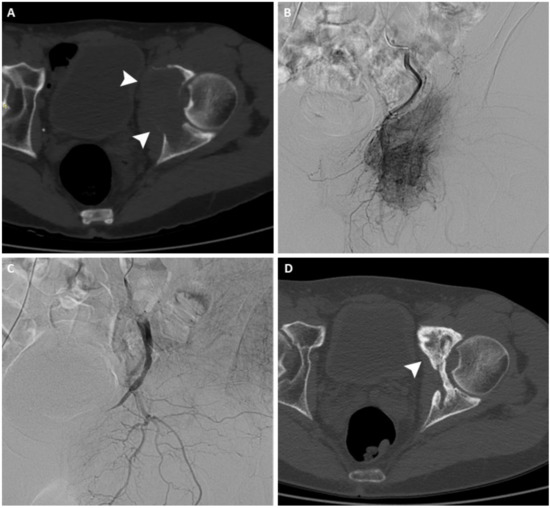

Figure 2.

(A) PET/CT scan of a 56-year-old woman, which shows an intense uptake of 18F-FDG in correspondence with a painful vertebral metastasis from breast cancer in the body of T7 (arrowhead). (B) Radiofrequency ablation of the lesion performed through a transcostovertebral approach.